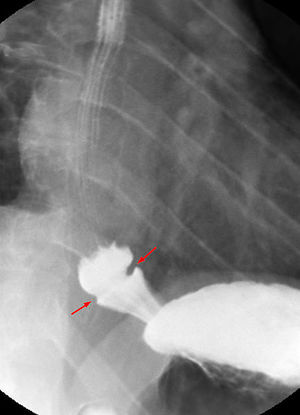

Schatzki ring

- Schatzki Ring: mucosal or muscular tissue ring

- Barium swallow